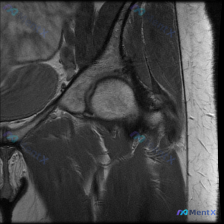

这个髋关节MRI病例,临床怀疑盂唇病变,但影像结果有争议

最近看到一个髋关节MRI病例,临床高度怀疑盂唇病变,但单一切面(T2冠状位)影像结果有点意外。先放影像分析的关键信息,大家一起讨论:

影像所见:

- 股骨头、股骨颈、髋臼形态正常,皮质连续,骨髓信号无异常

- 关节间隙正常,无狭窄或增宽

- 盂唇结构清晰,信号均匀,未见撕裂、退变或囊肿

- 周围软组织(臀肌、肌腱、关节囊)信号无肿胀,无关节积液

临床背景: 患者主诉髋部疼痛,临床怀疑盂唇病变,但影像结果和临床判断之间有一定矛盾。